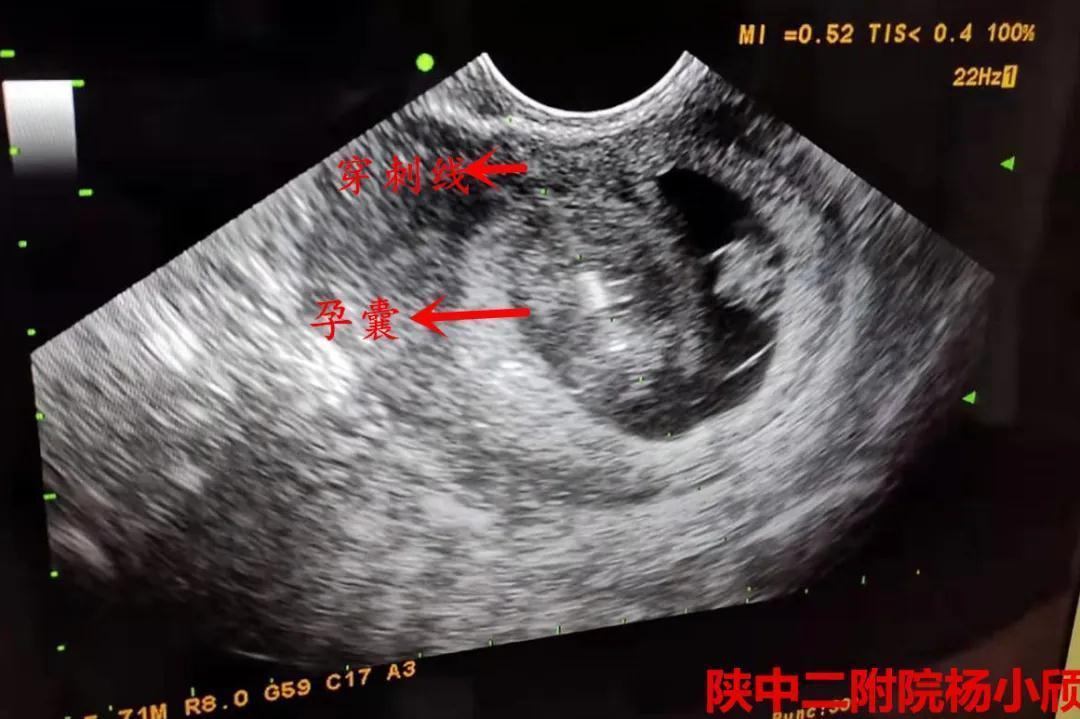

术前超声

在积极完善术前相关检查,排除手术禁忌症,充分告知患者及家属三胎妊娠的风险,签署知情同意书后,3月20日下午,杨小颀亲自操刀为患者实施了经阴道B超引导下选择性胚胎减灭术。手术顺利完成,病人病情平稳。术后24小时阴超提示,减胎孕囊胎心停止。7天后复查彩超提示,两胚胎存活,一胚胎停止发育。这标志着这台高难度的减胎手术圆满完成,达到预期效果,也再次彰显了陕西中医药大学第二附属医院(西咸新区中心医院)生殖内分泌科在减胎术方面的巨大进步。